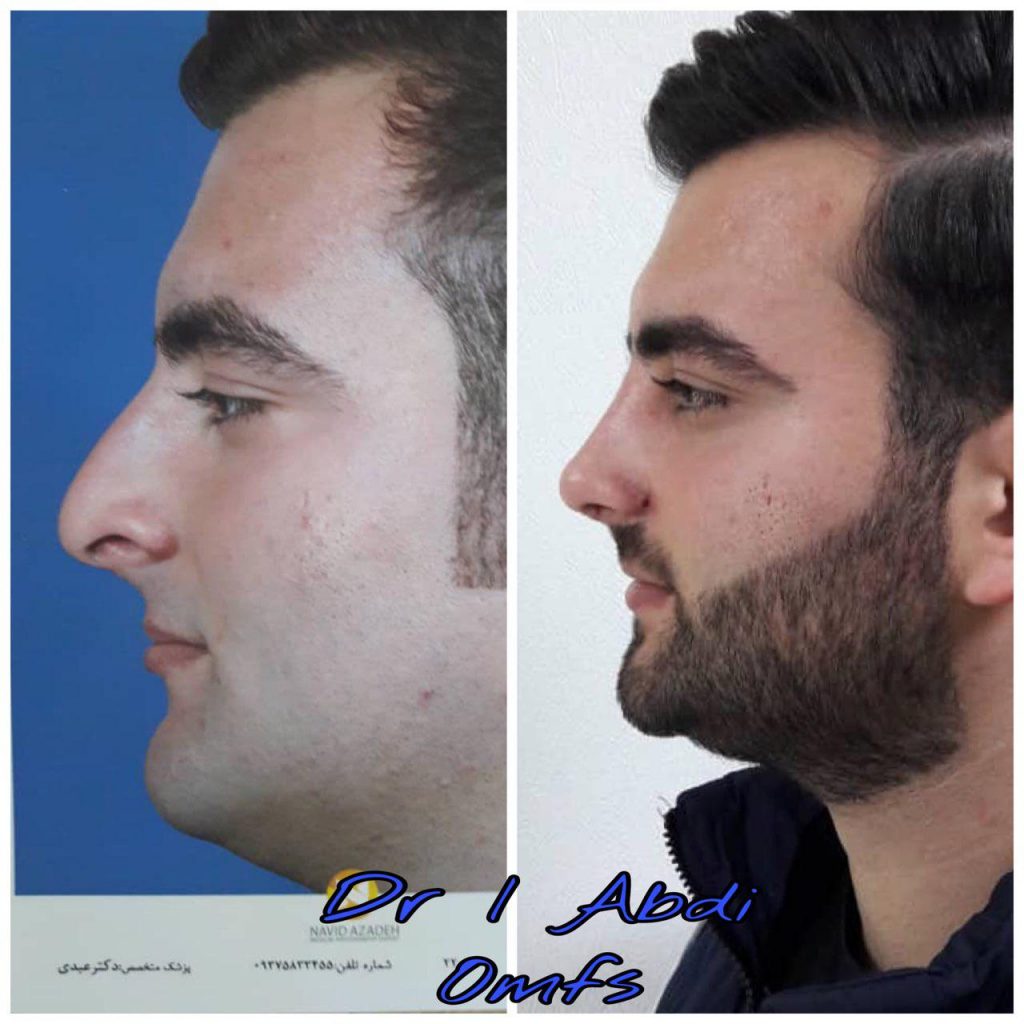

دکتر عیسی عبدی در رشت

دکتر عیسی عبدی در رشت

– متخصص جراحی فک , پلاستیک صورت و بینی

دکتر عیسی عبدی در رشت

جراحی فک , پلاستیک , صورت وبینی

جراحی ترمیمی و زیبایی فک و صورت و جمجمه و گردن